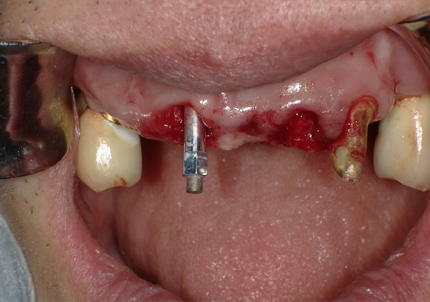

4.右上2番 S.S.T(ソケットシールドテクニック)

5.左上1番 S.S.T(ソケットシールドテクニック)

6.左上2番 S.S.T(ソケットシールドテクニック)

7.サージカルガイドによるインプラント埋入手術